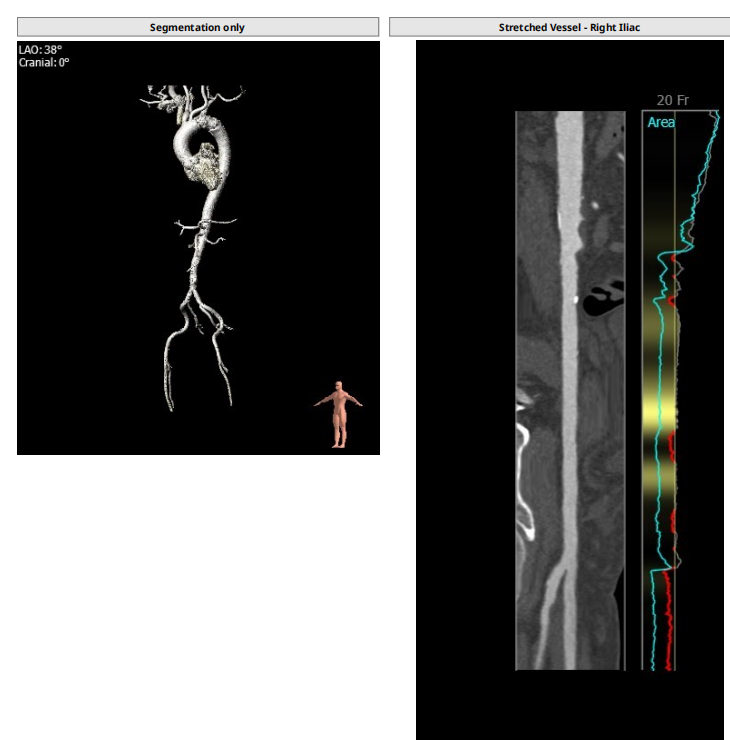

根部解剖: